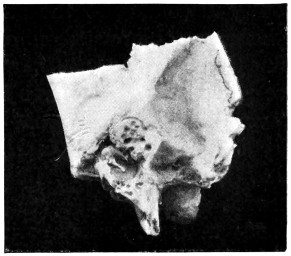

| 53. A basic fracture with laceration of both carotid arteries | 148 |

| 54. A basic fracture with laceration of the cavernous sinus | 149 |

| 55. A basic fracture with laceration of both lateral sinuses | 151 |